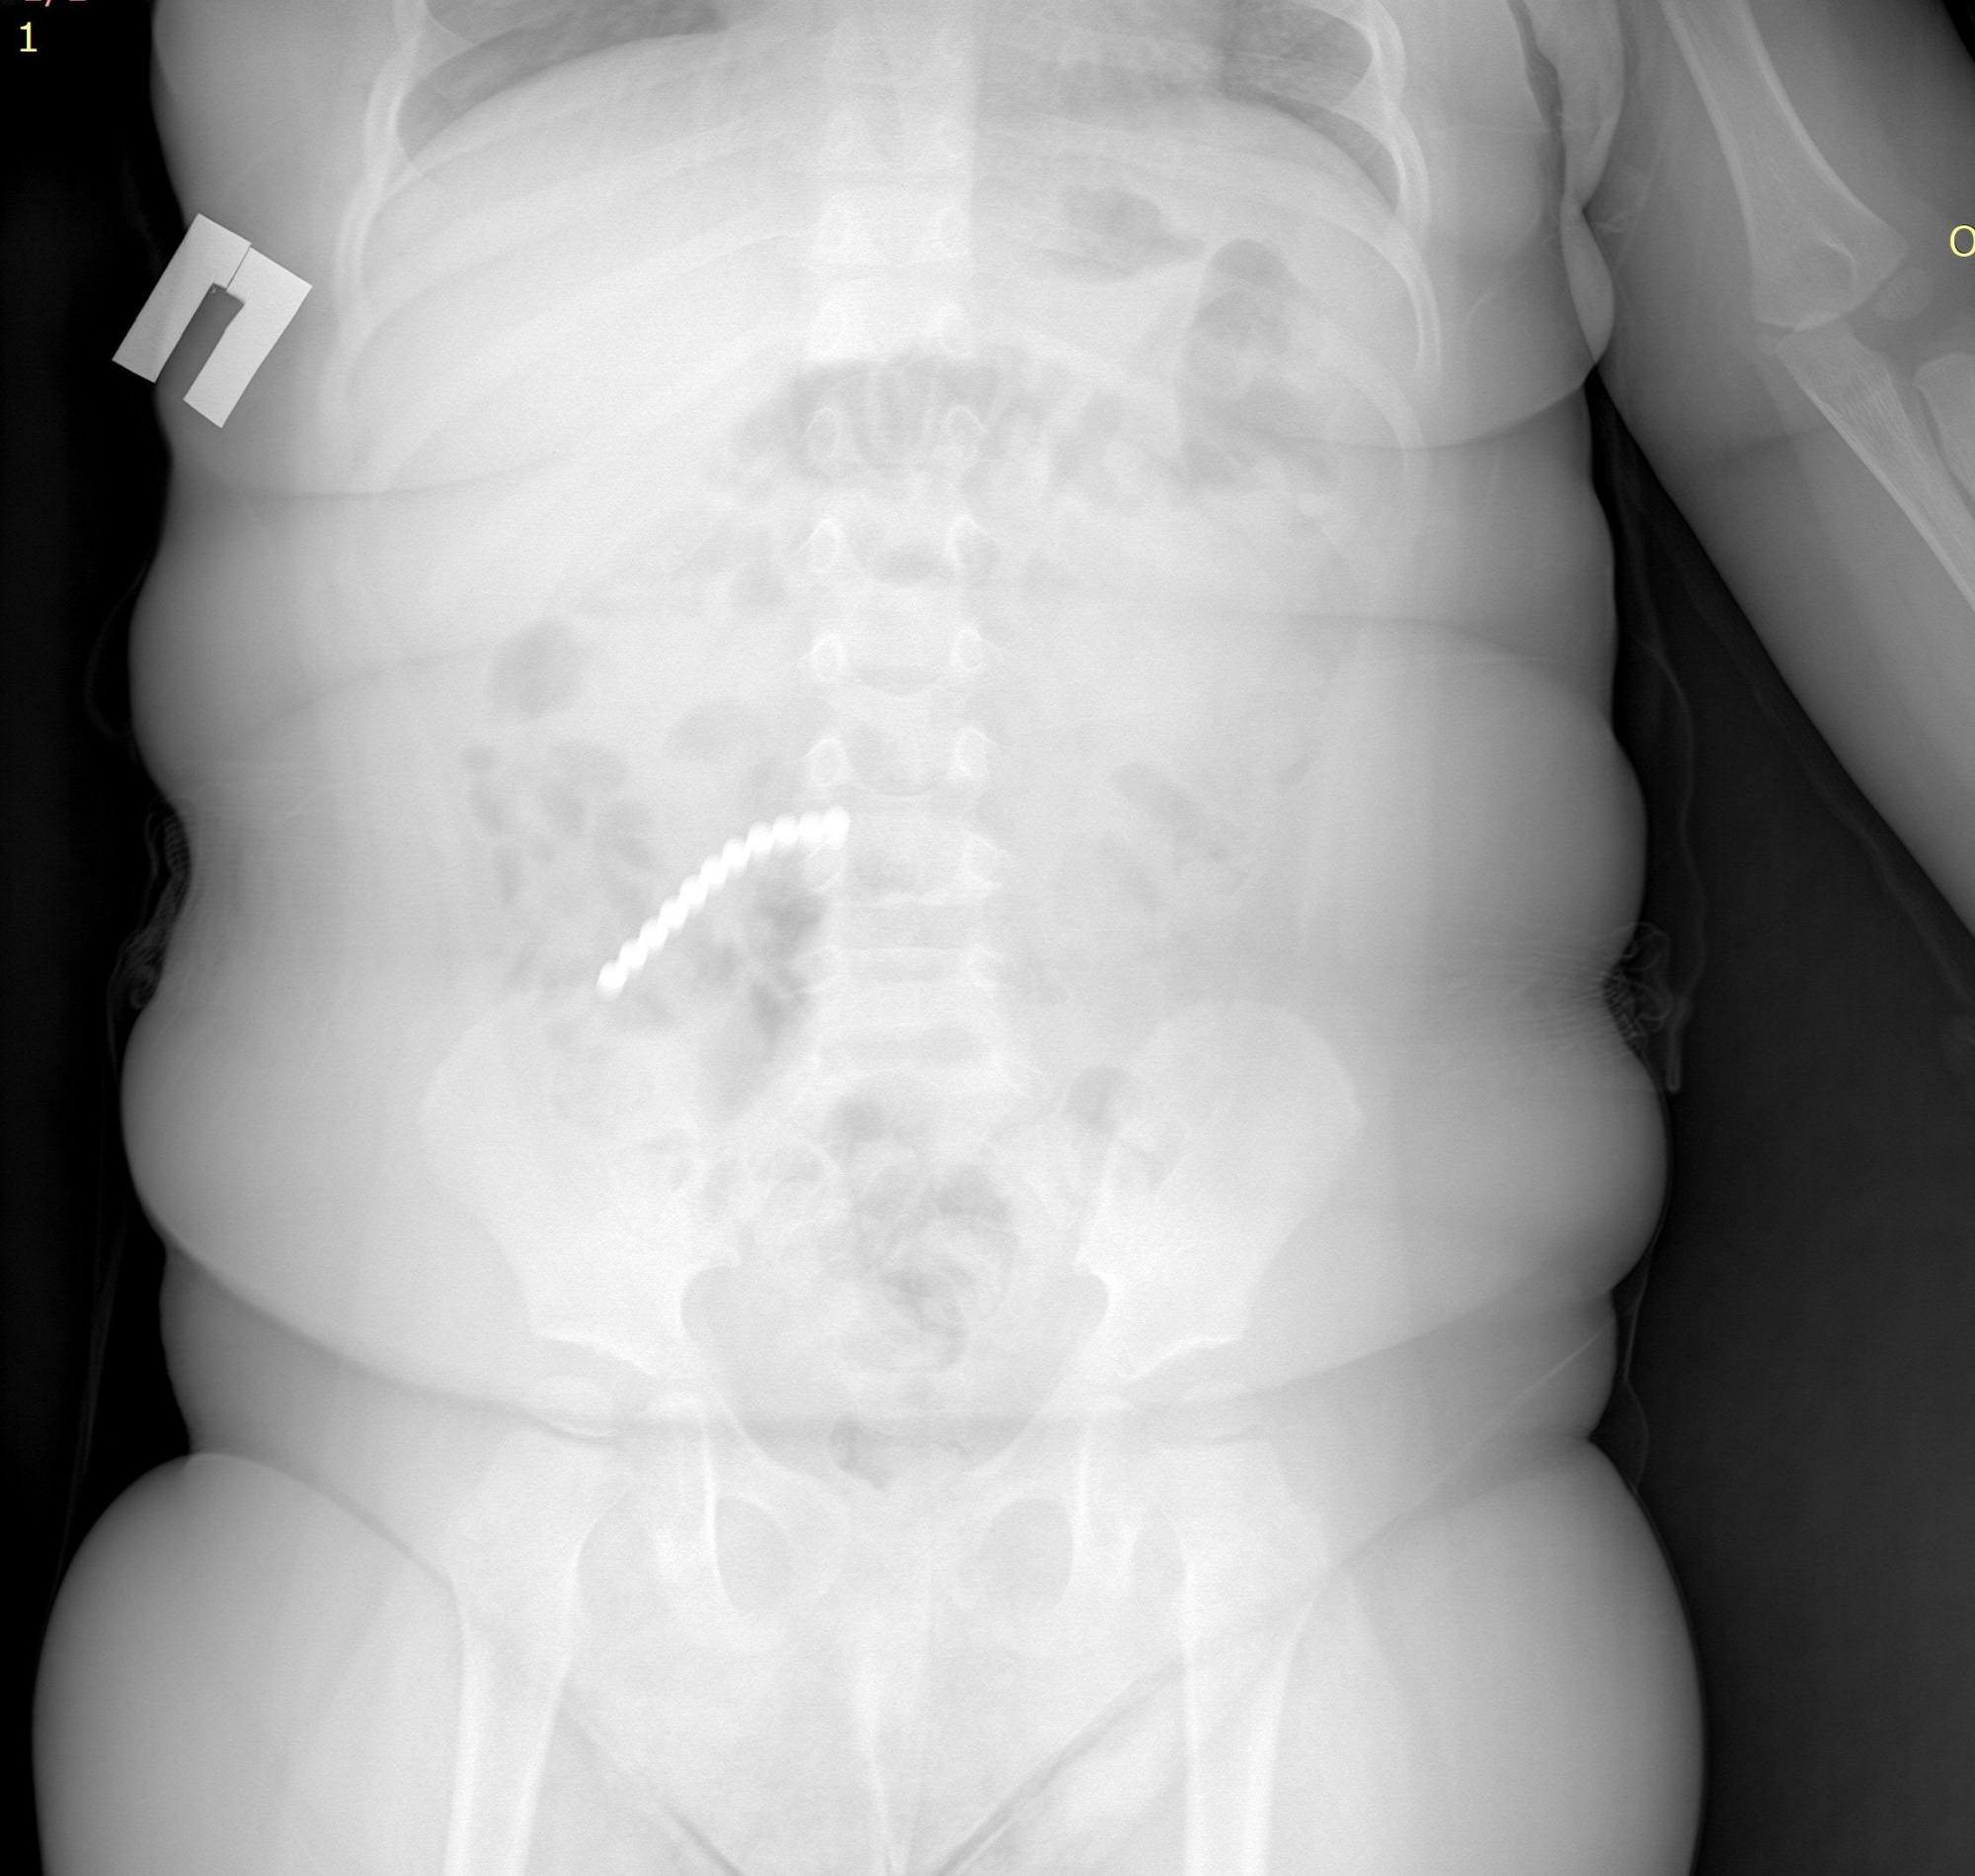

Врачи ДРКБ сообщили, что в начале февраля в Приемно-диагностическое отделение ДРКБ поступил ребенок с рвотой и ухудшением состояния. Рентгенография сразу выявила причину — 20 магнитных шариков от неокуба в пищеварительном тракте.

- Игрушка привела к перфорации кишечника, экстренному хирургическому вмешательству и резекции части тонкой кишки. Нам удалось удалить 9 штук магнитов эндоскопически (ФГДС). Однако остальные мигрировали по кишечнику, вызвав перфорацию. Петли тонкой, сигмовидной и слепой кишки слиплись между собой из-за магнитного притяжения, — пояснил врач-хирург-эндоскопист ДРКБ Булат Дондокович Шагдаров.

Ситуация потребовала перехода к открытой операции. Была выполнена лапаротомия. В ходе вмешательства хирурги обнаружили и устранили тяжелейшие последствия: ушили образовавшиеся межкишечные свищи, удалили участок тонкой кишки с перфорацией размером до 2 см. Отдельная опасность заключалась в том, что часть магнитов опустилась в аппендикс, который также пришлось удалить (аппендэктомия). Объем выполненного хирургического вмешательства отражает всю сложность случая.